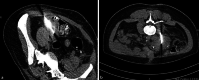

Background: In Germany pancreas transplants are performed in only a few selected and specialized centres, usually combined with a kidney transplant. Knowlegde of the indications for and techniques of transplantation as well as of the histopathological assessment for rejection in pancreas and duodenal biopsies is not very widespread.

Aim: To give an overview of the development and status quo in pancreas-kidney-transplantation in Germany summarizing the experience of the largest German pancreas transplant centre and to give a résumé of the results of histological diagnoses of biopsy specimens submitted between 06/2017 and 12/2020. Moreover, a detailed description and illustration of histological findings is included.

Material and methods: A thorough literature search for aspects of the history, technique and indication for pancreas transplantation was performed and discussed in the context of the local experience and technical particularities specific for the transplant centre in Bochum. The occurrence of complications was compared with international reports. Results of pancreas and duodenal biopsies submitted to Erlangen between 06/2017 and 12/2020 for histological evaluation, which were evaluated according to the Banff classification, were summarized. For a better understanding key histological findings of pancreas rejection and differential diagnoses were illustrated and discussed.